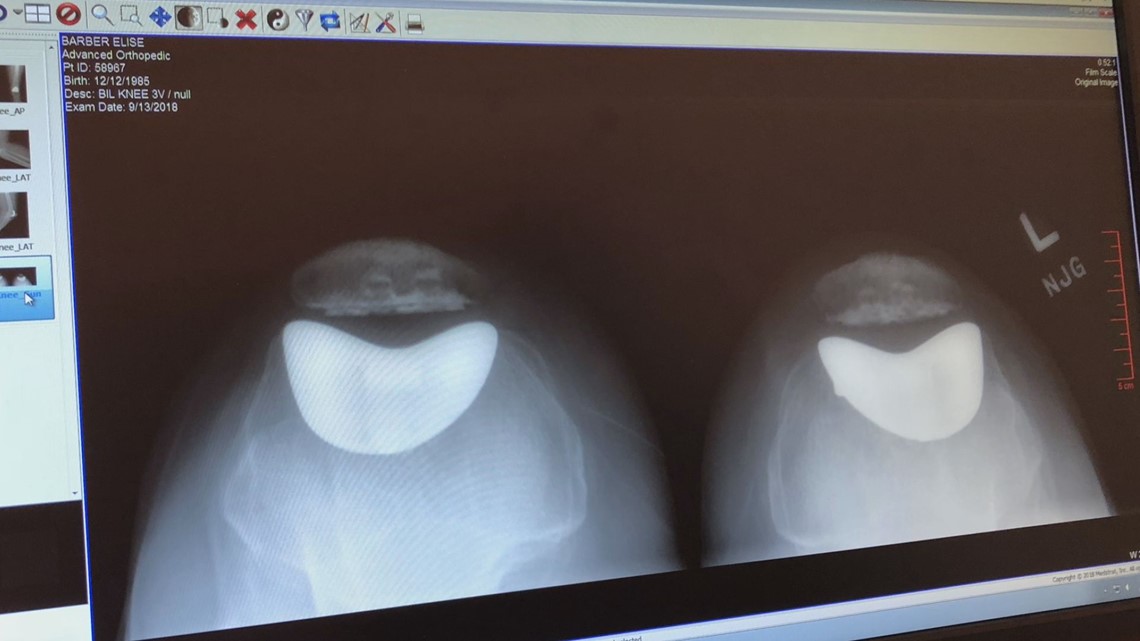

Metal allergies could lead to knee replacement complications Nickel Allergy In Joint Replacement We aimed to conduct a scoping review to clarify the management of. Orthopaedic implants contain nickel because of its ability to provide increased strength and durability. However, if patients develop metal allergy following their primary tka, the evidence presented supports revision surgery with hypoallergenic components with satisfactory. The most common form of all metal hypersensitivity is allergic contact dermatitis (acd). Nickel Allergy In Joint Replacement.

From www.9news.com